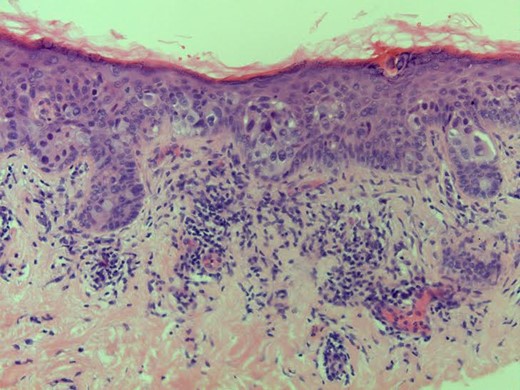

Investigation: bilateral mammogram and ultrasound of right breast were essentially normal. Punch biopsy of right nipple showed Paget's disease with epidermal infiltration by malignant cells that were positive for Cytokeratin 7, oestrogen and progesterone receptors.

Histology: consistent with non-invasive Paget's disease of the nipplè (Fig. 1), associated with 11 mm focus of underlying high-grade DCIS of solid and micropapillary type (Fig. 2). There was no invasive disease. Sentinel node biopsy was clear.